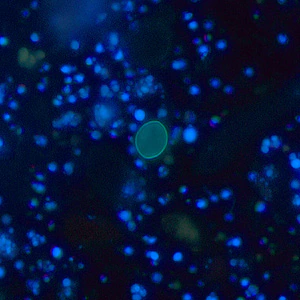

A 25-year-old refugee from Myanmar was screened for parasites at a local clinic in Tennessee. Stool specimens were collected in 10% formalin and polyvinyl alcohol (PVA) and sent to the state health laboratory for ova and parasite (O&P) work-up. Figures A–D show what was observed in a concentrated wet mount made from the formalin-preserved stool. Figures A and B show what was observed under brightfield microscopy; Figures C and D show the same fields, respectively, observed under UV microscopy. All images were captured at 400x magnification. The objects of interest measured on average 17 micrometers long by eight micrometers wide. What is your diagnosis? Based on what criteria?

Figure C